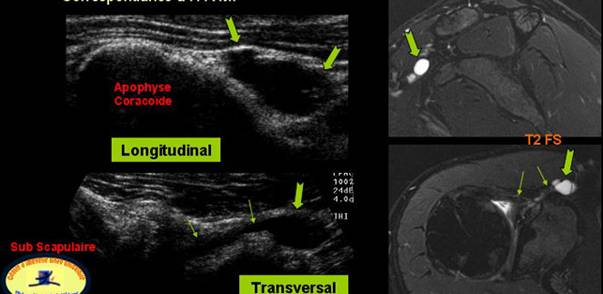

CHIST SINOVIAL GLENO HUMERAL ANTERIOR

DURERI SCAPULARE ANTERIOARE

STRUCTURA CHISTICA, TRANSSONICA,SITUATA DEASUPRA APOFIZEI CORACOIDE PRELUNGINDU-SE CU UN COLET PANA IN RECESUL SUBSCAPULAR